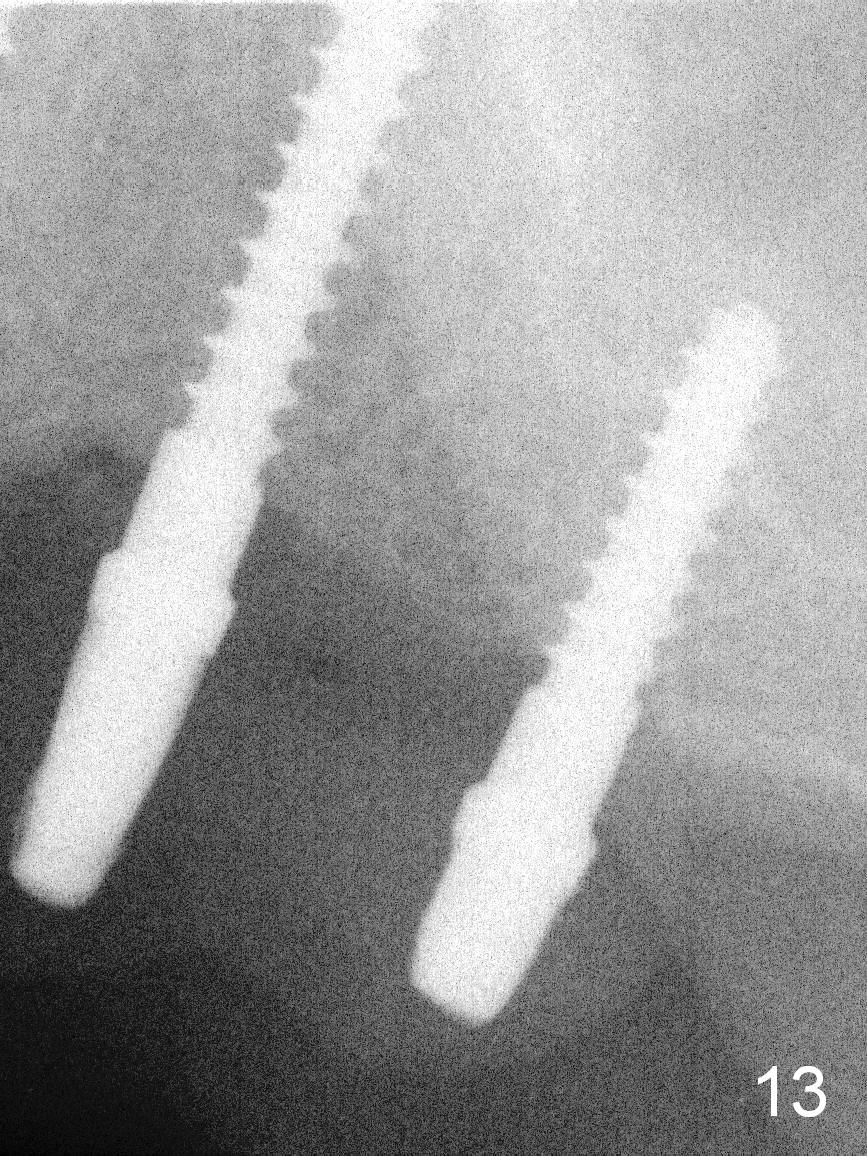

The patient returns for final restoration 3.5 months postop; it appears that the implants have osteointegrated (Fig.12,13). After reprep, there is no gross buccal plate atrophy at #10 (Fig.14).

Six months post cementation, the tooth #9 becomes symptomatic. Is it possible that the implant at #10 is too close to the root of #9? It is asymptomatic after pulpotomy, but the tooth fractures equi/supragingivally. Two PAs taken while RCT show osteointegration at #10-12 (Fig.18,19). While the bone density increases at #10 regular implant, there is minimal bone loss around the 1-piece implants 13 months post cementation (18 months postop, Fig.20,21). The gingiva remains healthy 19 months post cementation (Fig.22). 76岁病人突然打电话说一个植牙牙冠松动,其实9号牙(自然牙)折裂,6,10-13号牙植牙好像没有骨质吸收(图二十三至二十五),10-13牙位牙龈健康(图二十六,行使功能五年)。9号牙牙冠重新粘固后,显示前牙深覆合,深覆盖(图二十七,二十八)。如果再次脱落需要植牙,选择一段式有助于植入和修复,因为植体和基台直径小。两段式植牙相对基台直径至少4,或者4.5毫米,前牙修复显得笨重。由于9,10牙根和植体接近,9号牙植体需要偏小而长,3x14或者15毫米(图二十九)。